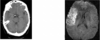

24

Q

What is the likely diagnosis in this MRI with contrast

A

Tumor: lit up because it is vascularized

If it was an abscess it would be dark because it wouldn’t be vascularized